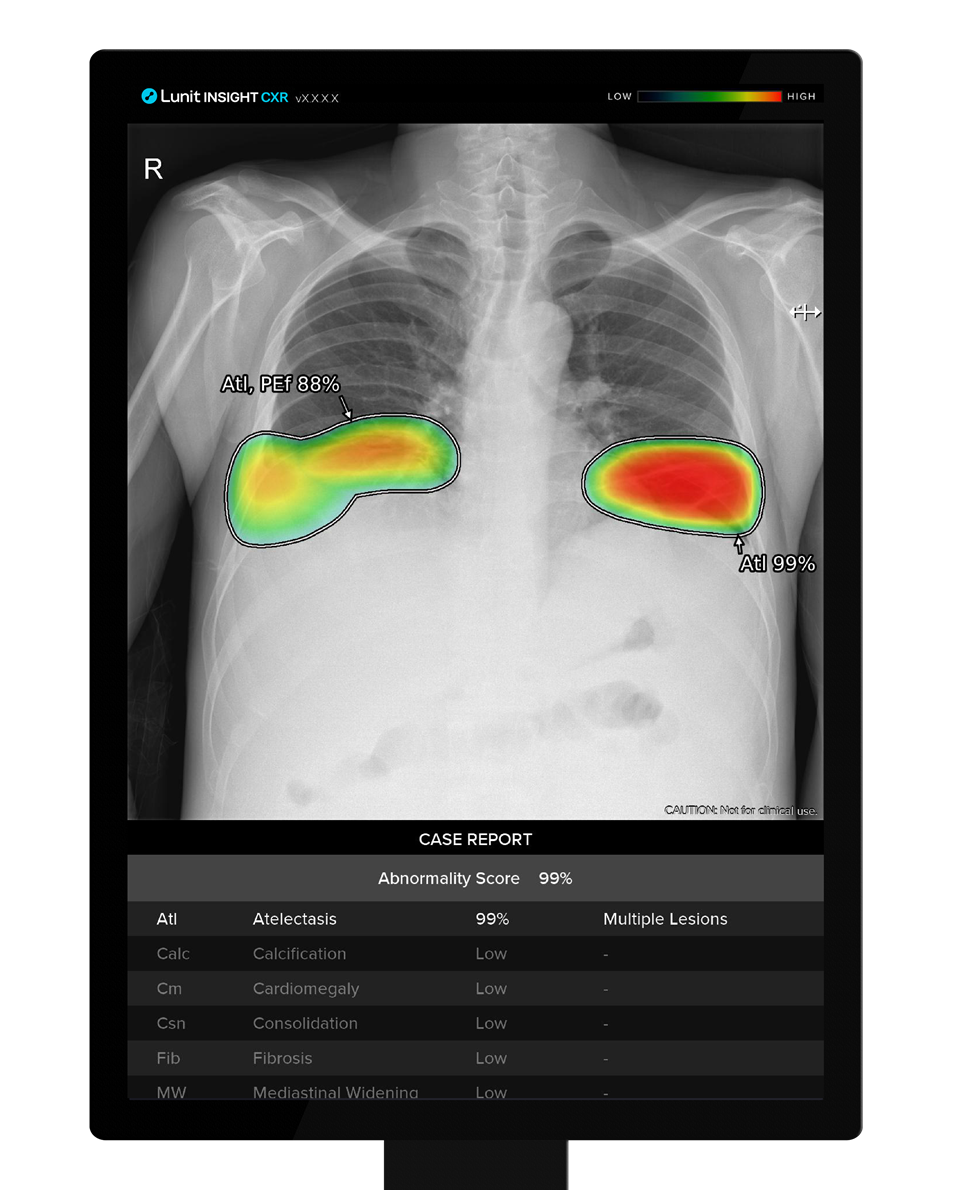

의료 인공지능(AI) 기업 루닛(대표 서범석)은 흉부 엑스레이 AI 영상분석 솔루션 '루닛 인사이트 CXR'을 브라질 내 교도소 세 곳의 수감자에 적용한 결과, 세계보건기구(WHO)의 결핵 검진 성능기준에 부합하는 결과가 나왔다고 15일 밝혔다.

그 결과 루닛 인사이트 CXR은 AI 모델의 성능평가 지표인 ‘수신자 조작 특성’ 분석에서 결핵 검출 능력이 0.91로 나타났다. 수치가 1에 가까울수록 신뢰도가 있는 것으로 평가되며, 루닛 인사이트 CXR의 수치는 연구에 사용된 3개 솔루션 중 가장 높았다.

루닛은 이는 세계보건기구가 정한 결핵환자분류 민감도, 즉 양성 판별률 기준인 90%에 부합하는 수치라고 밝혔다. 루닛 인사이트 CXR은 나이, 흡연 여부, 결핵증상 유무 등 다양한 조건에서 좋은 성능을 보였다.